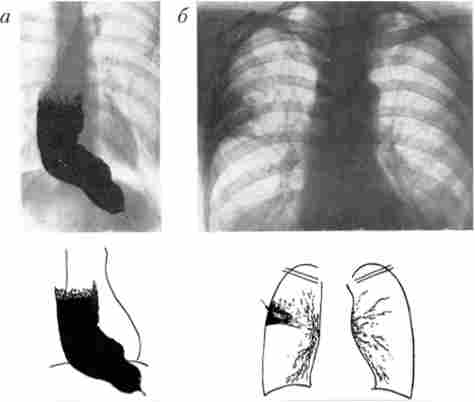

Головний рентгенологічний симптом кардіоспазм - виявлення конічного звуження дистального відділу стравоходу, яке описується як симптом «мишачого хвоста», «пташиного дзьоба» і т. Д. Вищерозміщені відділи стравоходу при цьому зазвичай розширені відповідно стадії захворювання. Дилатація стравоходу може бути виражена дуже значно. При рентгеноскопії виявляють нерозкрите кардії при акті ковтання, порушення перистальтики стравоходу. Нерідко виявляють відсутність газового міхура шлунка і рентгенологічні ознаки аспіраційних легеневих ускладнень кардіоспазм (рис. 9.2).

Рентгенологічні симптоми кардіоспазм

Мал. 9.2. Рентгенологічні симптоми кардіоспазм:

а - стравохід значно розширений, подовжений і зміщений вправо; дистальний його відрізок різко звужений, газовий міхур шлунка відсутній; 6 - праворуч у верхній частці легені визначається пневмосклероз як наслідок багаторазових аспіраційних пневмоній